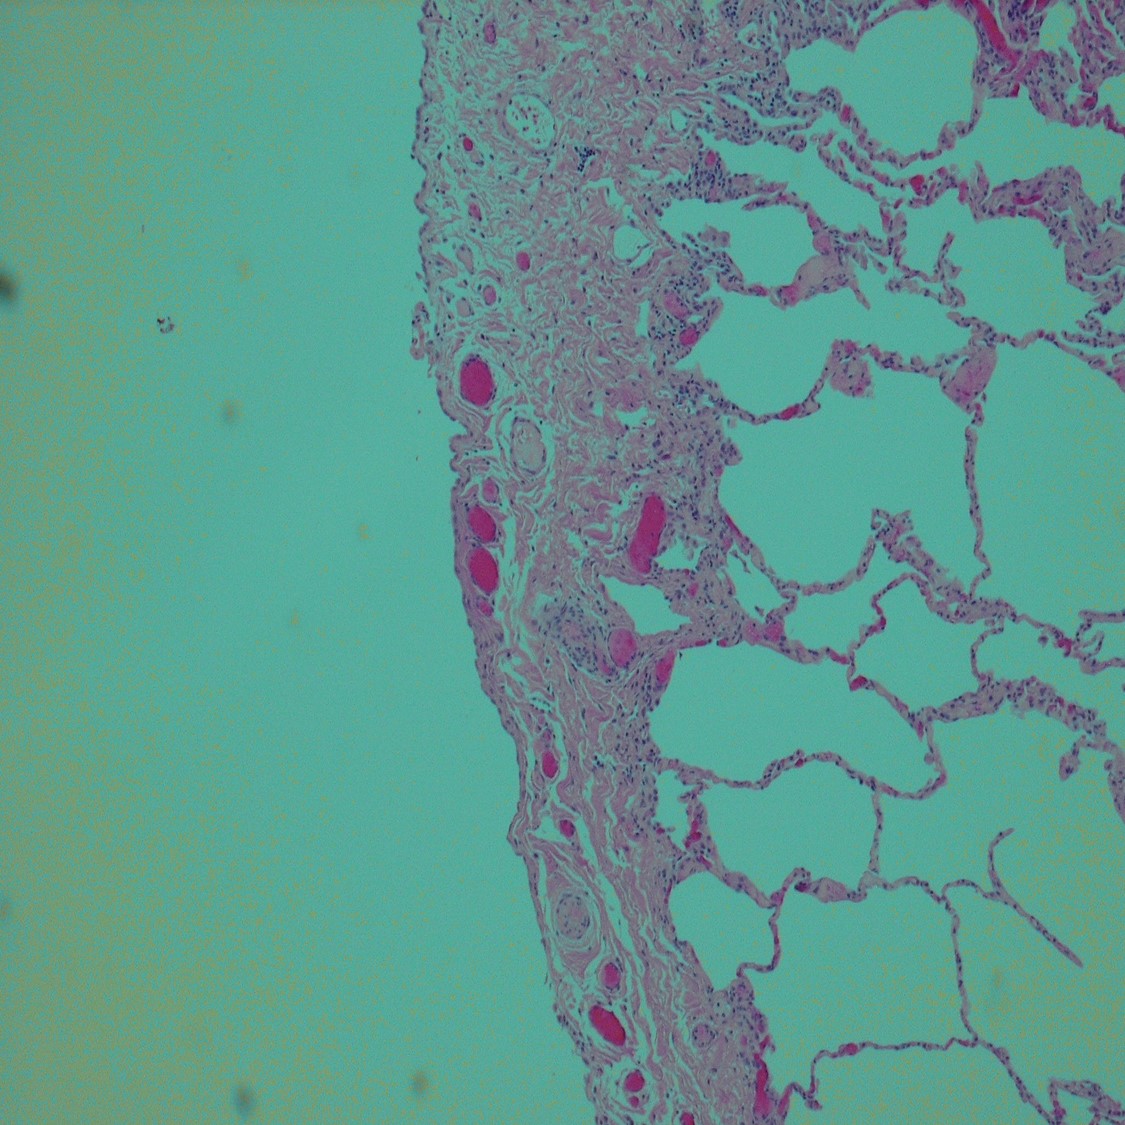

This 39-year-old Hispanic woman, a never smoker, underwent thoracotomy and...

Clinical History: